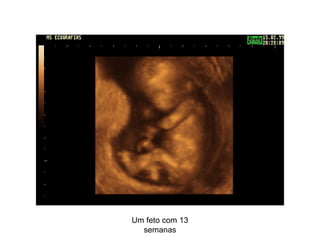

O documento descreve o desenvolvimento de um feto em diferentes estágios de gestação, desde 9 semanas até o nascimento, e depois mostra imagens de ecografia de uma pessoa desde bebê até os 80 anos para ilustrar o ciclo completo da vida.